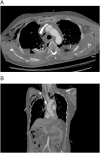

Blunt traumatic transection of the innominate artery is rare. We describe a case of a 36-year-old male who presented to our Emergency & Trauma Center after being struck by a motor vehicle at high speed. Computerised Tomography (CT) scanning after the patient was stabilised facilitated the prompt diagnosis of the injury. The patient underwent open repair by midline sternotomy, with debranching of the innominate artery, using hypothermic circulatory arrest as a neuroprotective measure. The patient was successfully extubated on post-operative day 3, without neurological deficit. We provide our experience as an option for treating any patient that presents with such an injury.